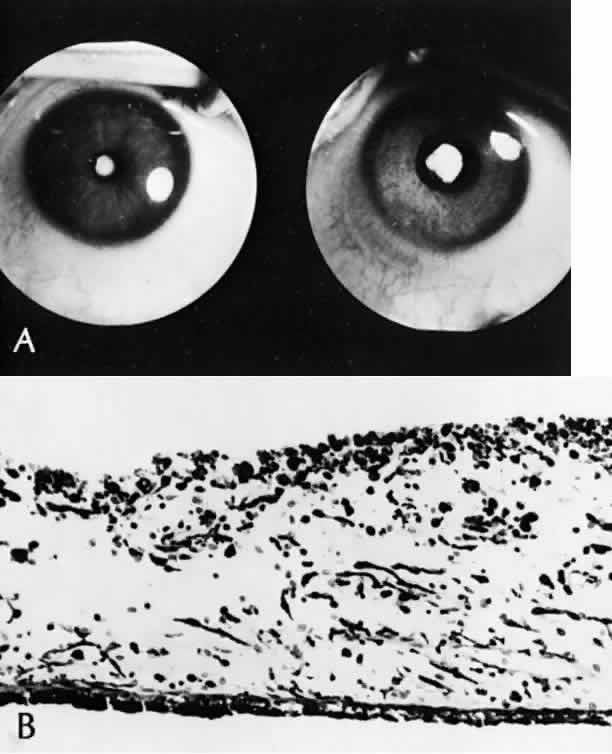

The iris can be leathery and dilates poorly in response to mydriatics. Histologically, the iris has a poorly developed dilator muscle, with necrosis of the iris and ciliary body epithelium and chronic nongranulomatous inflammation of the stroma (Fig. 16).118 This inflammatory reaction sometimes becomes clinically manifest after cataract extraction, which can lead to cyclitic membrane formation and retinal detachment.119

Fig. 16. Rubella. A. Same eye before (left) and after (right) maximal dilatation with mydriatics. A dense nuclear cataract can be seen in the minimally dilated pupil. Iris is leathery and difficult to dilate (SEI 73–631). (Courtesy of Dr. HG Scheie) B. Iris is atrophic, is infiltrated with plasma cells and lymphocytes (chronic nongranulomatous iritis), and shows a loss of the dilator muscle (H&E, × 130 [SEI 79-36]). (Yanoff M, Schaffer DB, Scheie HG: Rubella ocular syndrome: Clinical significance of viral and pathologic studies. Trans Am Acad Ophthalmol Otolaryngol 72:896, 1968)